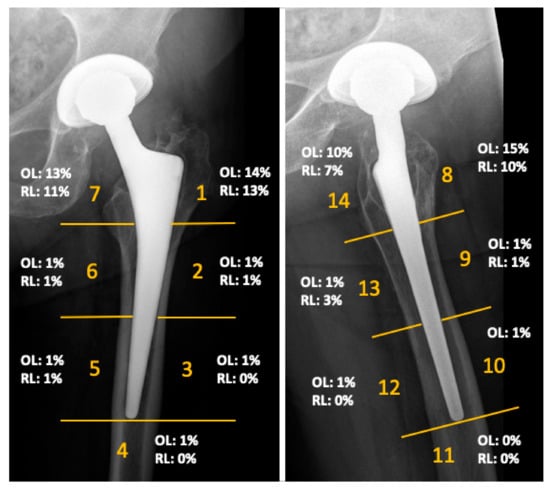

The mean Harris Hip Score of the cohort was 90 points (range 40 to 100) at the time of follow-up. The mean inclination angle of the acetabular component was 42 degrees (range 29–50 degrees). No femoral component showed radiographic signs of loosening. Radiographs demonstrated femoral osteolysis in 23% of the hips and radiolucent lines > 2 mm in 13% of hips. Osteolysis and radiolucent lines were predominantly located in the proximal Gruen zones. Their distribution is illustrated in Figure 3. Periacetabular osteolysis was rarely seen, with an overall frequency of 2%. MARS-MRI demonstrated pseudotumor formation in 27 of the 66 investigated patients (41%). ARMD were generally small and predominantly cystic in nature. More detailed results of this investigation were previously published in another study of this research group [13].

Figure 3.

Results of the radiographic evaluation showing the distribution of radiolucent lines (RL) and osteolysis (OL), as seen on anteroposterior and lateral radiographs according to Gruen zones at a mean follow-up of 14 years.